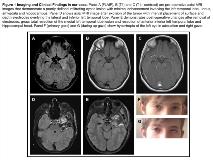

Rationale: Intracranial monitoring has evolved as an essential step in identifying the ictal onset zone in epilepsy surgery. However, this process is not devoid of significant risks. Though frequently observed complications associated with electrode placement include extra-axial fluid collections, hemorrhage, infection, infarcts, and edema; cranial nerve complications are not as common (Table 1). To our knowledge, isolated fourth nerve palsy as a result of electrode complications has not been reported. Methods: Here, we report a case of isolated acquired fourth nerve palsy, subsequent to subdural electrode placement that resolved spontaneously over the next six months. Results: A 13 year-old boy with drug-resistant focal epilepsy was evaluated for epilepsy surgery. Seizure onset occurred at age 7 years, with semiology described as brief staring episodes, occasionally with bilateral tonic-clonic activity. MRI brain with gadolinium revealed a left anteromedial temporal lobe lesion with calcifications, cysts, and small foci of enhancement, concerning for glioma (Fig 1A-C). Prenatal, birth, developmental, and family history were unremarkable. Neurological exam, including a detailed neuro-ophthalmologic exam, was also unremarkable. He underwent a Stage I left temporal lesionectomy, followed by placement of a 48-contact fronto-temporal grid, two 4-contact and one 6-contact strip along the temporal resection bed, and one 8-contact depth electrode in the mesial temporal lobe (Fig 1D). Intracranial EEG revealed multifocal epileptiform discharges over the left temporal lobe and the fronto-parieto-temporal grid contacts. As EEG also revealed frequent subclinical seizures with left anterior temporal lobe ictal onsets, he underwent an elective anterior medial temporal lobectomy.Immediate post-operative course was uneventful. Pathology revealed features of a low grade tumor, with features of both ganglioglioma and Dysembryoplastic Neuro-Epithelial Tumor. One week post-operatively, he developed episodic left eye hyper-deviation, with no diplopia or associated visual symptoms. A detailed neuro-ophthalmology evaluation revealed an intact pupillary examination, no afferent pupillary defect, no change in visual acuities, and intact visual fields with no scotoma or hemianopsia. Ocular motility exam revealed intact saccades and pursuits in cardinal directions, and no nystagmus or diplopia in primary position. However, evidence of left hypertropia in attempted left gaze, left superior oblique weakness with overaction of the left inferior oblique, and a subtle head tilt to the right consistent with a left fourth nerve palsy was noted (Fig 1F-G).  A repeat MRI brain was unremarkable. His symptoms spontaneously resolved over the next six months.  Conclusions: In our case, no structural lesions were demonstrated post-operatively. We postulate that the trochlear nerve palsy occurred either as a result of direct electrode placement or from traction injury of the fourth nerve secondary to the temporal lobectomy. We recognize that it is difficult to determine whether one or both of these factors contributed to the fourth nerve palsy in our patient. Nevertheless, no cases of trochlear nerve palsy secondary to either of these causes have been reported in the pediatric population. While a definitive underlying etiology in our case remains speculative, our case highlights that fourth nerve palsies can occur as a complication of intracranial invasive EEG monitoring, and underscores the importance of identifying this for appropriate patient counseling and management. Funding: N/A